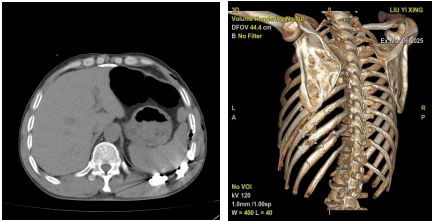

患者男性,54岁,在施工时不慎从高处坠落,左季肋区着地,随即出现左季肋区疼痛,呼吸时加重。随即患者被送来北京市垂杨柳医院急诊完善肢带骨CT提示:左侧第8-12肋骨骨折,部分断端移位明显,其中第8-11肋均有两处骨折,第9肋完全离断,错位明显。查体左侧胸壁明显塌陷,胸壁软化,可见浮动胸壁,患者疼痛剧烈,呼吸受限,不能下地活动,伴胸闷、憋气。经胸外科医师讨论后,决定给予患者在微创胸腔镜下行肋骨骨折复位内固定术。

术前